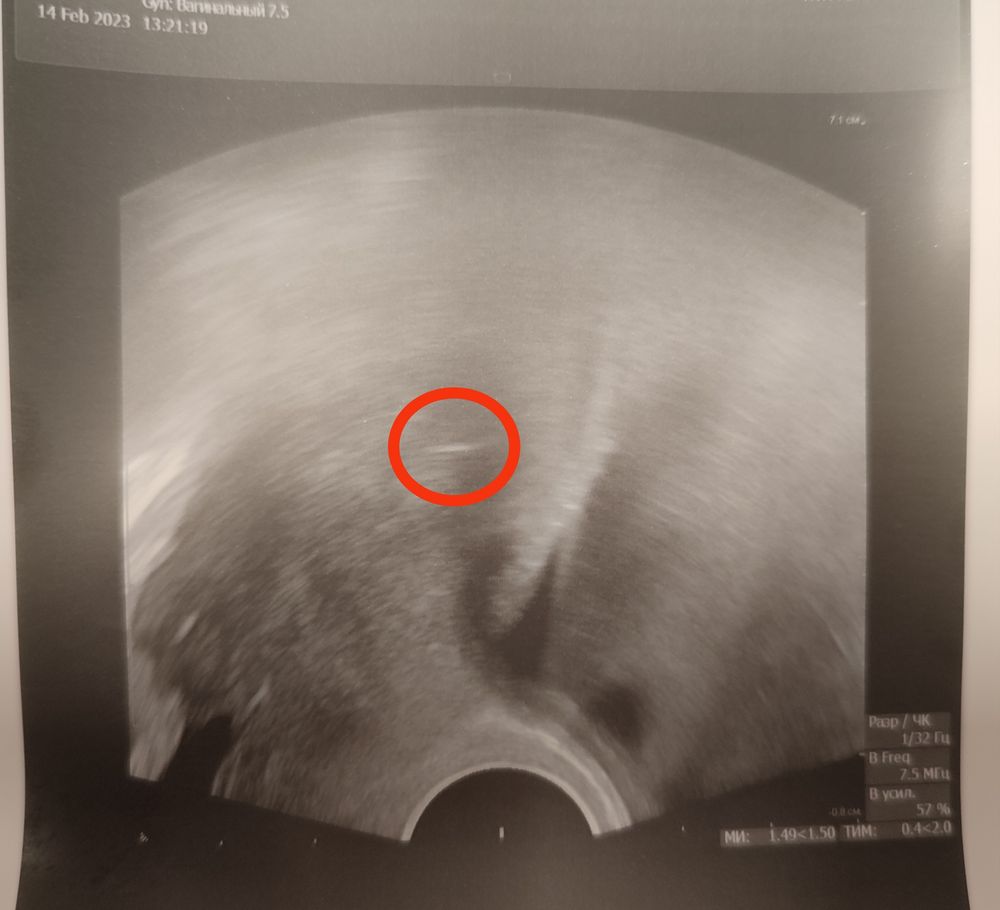

Ровно год назад была подсадка, мой 2-й Крио протокол. Удачный! А сегодня нашей малоежке уже 3+ месяца ❤️🥰❤️